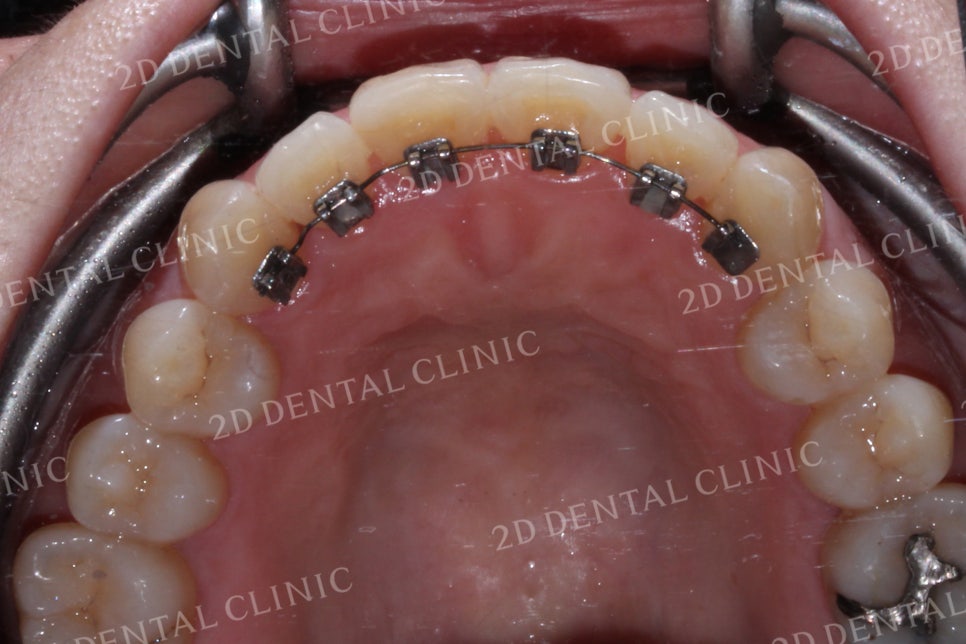

상악의 설측면 사진입니다.

위에서 말했던 것처럼

측절치가 설측면으로

과도하게 들어와 있는 모습입니다.

상악의 설측면에서 명확하게 느껴졌던

측절치의 경사가 교정 후 정상 경사로

바뀐 모습입니다.

반대교합 역시 치열이

가지런하게 바뀌면서

올바른 교합 상태로 바뀌었네요!